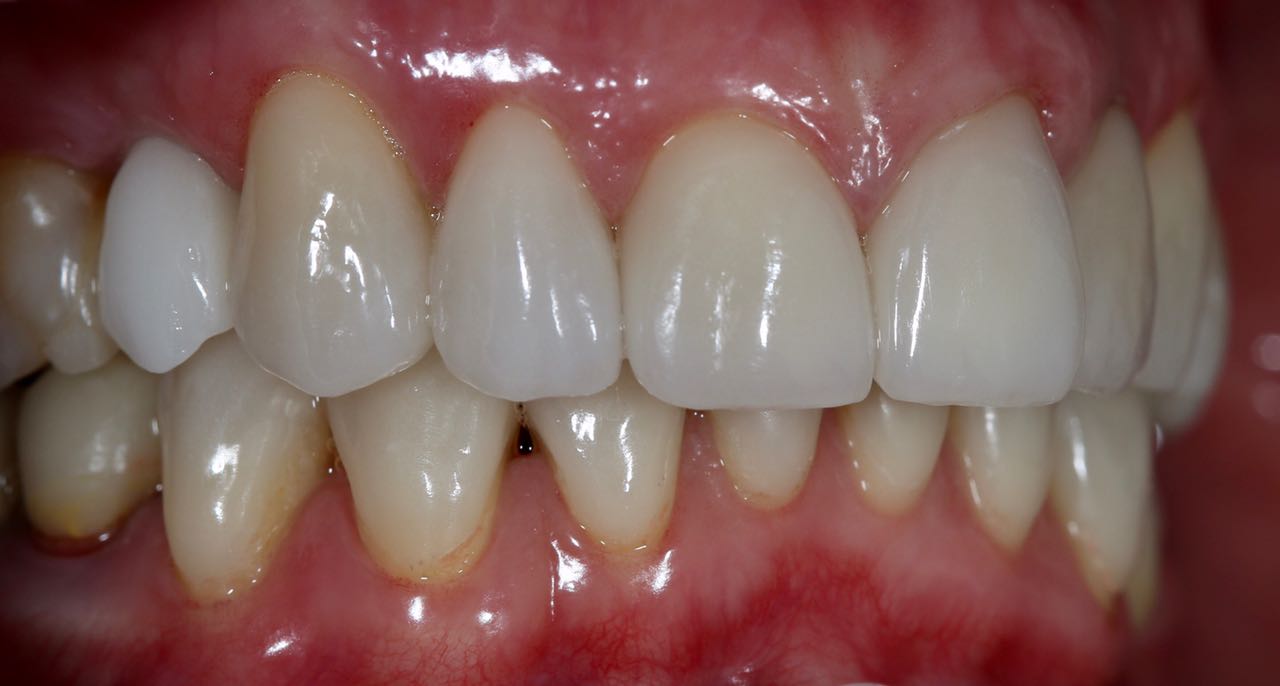

Белые виниры BLEACH

Все чаще стали поступать заказы на виниры цвета BLEACH. Очень красивый результат. Улыбка становится очень красивой.

Это виниры на рефракторе . 12 зуб коронка на оксиде циркония.